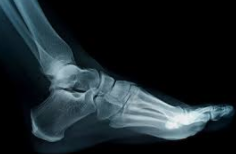

복숭아뼈 부음

복숭아뼈가 붓는 현상이 있으면 조기에 치료를 잘 못합니다. 잘보일듯하지만 생각보다 복숭아뼈 부은 상태를 발견하는건 쉽지 않아서 치료를 잘 못하시는 분들이 많은데요. 오늘은 복숭아뼈 부음 현상의 원인 및 치료방법에 대해 알아보겠습니다.

| 복숭아뼈 부음 발생 원인

1) 점액낭염

복숭아뼈에는 점액낭이라고 부르는 것이 있습니다. 점액낭은 관절이 있는 부위에 있는것인데 관절을 보호하기 위해 있는 앏은 주머니형태입니다. 점액낭 부위에 염증이 생기면서 복숭아뼈 부음 현상이 나타납니다.

점액낭염은 외상이 있거나 복숭아뼈에 반복적인 마찰이 일어나면 발생하기 쉬우며 세균에 감염이 되었을때도 발생될 수 있습니다.

보통 점액낭염은 통증이 심하진 않습니다만 점액낭에 종양이 발생되면 악성종양이 될수 있기 때문에 발생된다면 병원에 반드시 방문하여 진단을 받으시는게 좋습니다.

2) 복숭아뼈 누공

누공은 발목을 접지르거나, 인대가 늘어나서 파열되었을때 나타나는데 해당 부위에 물이 차게 되면서 물혹처럼 보일때가 많습니다. 붓기의 상태가 아주 크다면 관절 누공으로 의심해볼 필요가 있습니다.

| 복숭아뼈 부음 치료방법

물혹의 경우에는 주사기로 물을 빼주는데 이러한 방법은 근본적인 치료 방법이 아니기 때문에 재발이 잘되고 자주 물을 빼내줘야하는 번거로움이 있습니다. 점액낭염이라면 소염제등 염증을 없애주는 약을 처방받아 복용하기도 합니다. 관절 누공이라면 뼈에 문제가 생긴 것이기 때문에 정형외과에서 진단을 받으시고 치료를 받는것이 좋습니다.